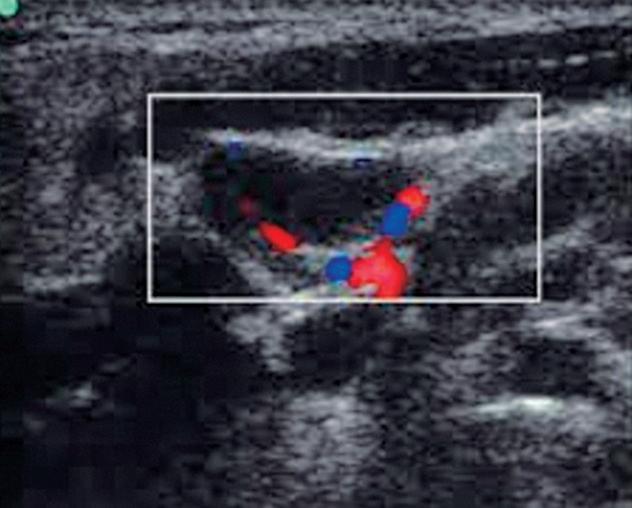

Fig. 4-17. Vascularização usual do linfonodo – padrão hilar (central).

Fig. 4-20. Vascularização aberrante em linfonodo atípico.